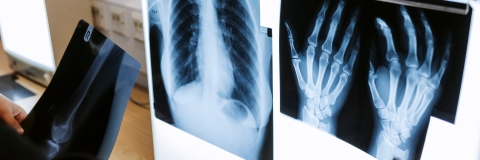

Discover the impact our research teams are making in collaboration with hospitals, charities, other universities and health trusts

Our research in health and wellbeing aims to improve the health of people and communities around the world.

The benefits of our ongoing health partnerships include providing healthcare staff and organisations with the training and technologies they need to succeed, finding better ways to share healthcare data to improve the patient experience, supporting students interested in a career in healthcare or research, and finding methods to improve advanced diagnosis of critical conditions.

Through our clinical health partnerships, we're working to better understand rare diseases, cancers, inflammatory and respiratory conditions, infection and oral health.